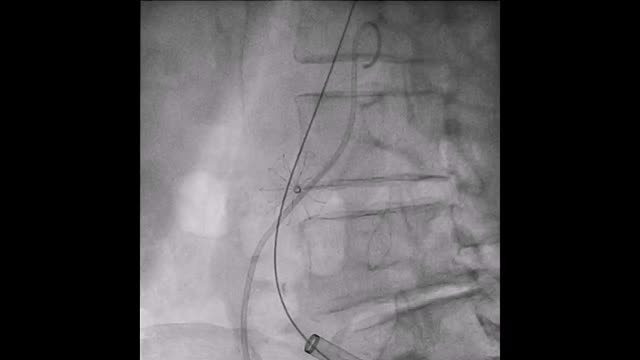

El paciente se traslada a la sala de hemodinamia donde se intenta la extracción del dispositivo. Se utilizan diferentes catéteres lazo de 10, 25 y 30 mm, así como lazos de fabricación con guías largas y cortas intentando movilizar el dispositivo desde diferentes accesos vasculares (acceso bifemoral 6 y 18 Fr y radial 6 Fr) (figuras de la 1 a la 4). Se produce como complicación disección de aorta abdominal con extensión a arteria ilíaca común derecha (figuras 5 y 6) y pérdida total del flujo en extremidad inferior ipsilateral con signos y síntomas de isquemia arterial aguda, por lo que el paciente es trasladado de forma urgente al quirófano de angiología y cirugía vascular. Se realiza disección de aorta abdominal infrarrenal vía laparotomía media con aortotomía longitudinal en el lugar de la localización del cuerpo extraño visualizándose el dispositivo migrado anclado a la íntima-media de la pared arterial. Se procede a su extracción y posteriormente se realiza cierre de aortotomía con parche de pericardio bovino fijando la disección y corrigiendo así el defecto (figuras de la 7 a la 9). El paciente sale de quirófano con pulso pedio bilateral y excelente perfusión distal.